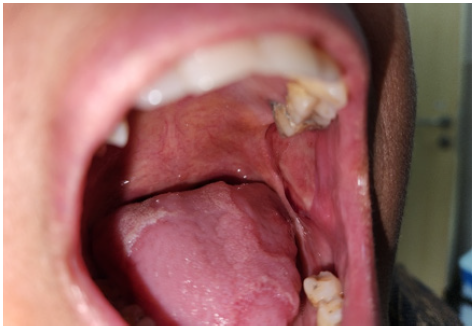

Introduction: Angina bullosa hemorrhagic is a benign, rare condition of oral cavity, characterized by a sudden onset blood filled blisters in mucosal of oral cavity which rupture and heals spontaneously without scarring, considered to present in 0.05% of cases of oral ulcer. It resolves spontaneously, but in 30% cases it has tendency to reoccur.

Case report: A 48-year-old female presented with sudden onset, self-resolving oral ulcer clinically diagnosed as Angina Bullosa Hemorrhagic following Ordioni et al. criteria for diagnosis.

Conclusion: Angina Bullosa Hemorrhagic is a rare, benign disease of oral cavity that rupture and heals spontaneously without scarring, often triggered by trauma or associated with systemic factors such as hypertension, diabetes or prolonged use of corticosteroid. Diagnosis is mainly clinical. Differentiation form vesicobullous, hematological disorder is essential to avoid misdiagnosis and unnecessary interventions.